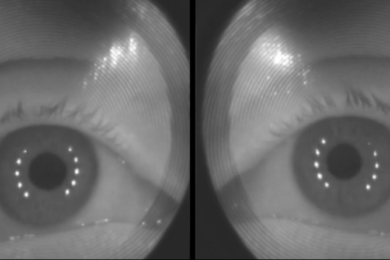

Amerykańska firma technologiczna Montana Gaize Inc. opracowała innowacyjne urządzenie, które na podstawie krótkiego skanu oczu jest w stanie stwierdzić czy dana osoba jest na...